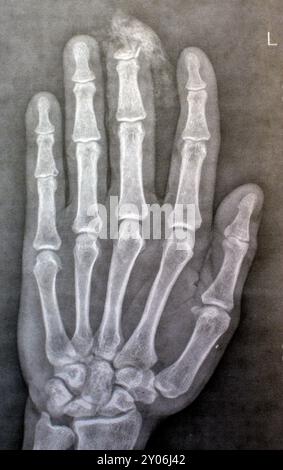

Plain X-Ray reveals distal tip amputation of distal phalanx of the

Plain X-ray Reveals Distal Tip Amputation Stock Photo 2499162053